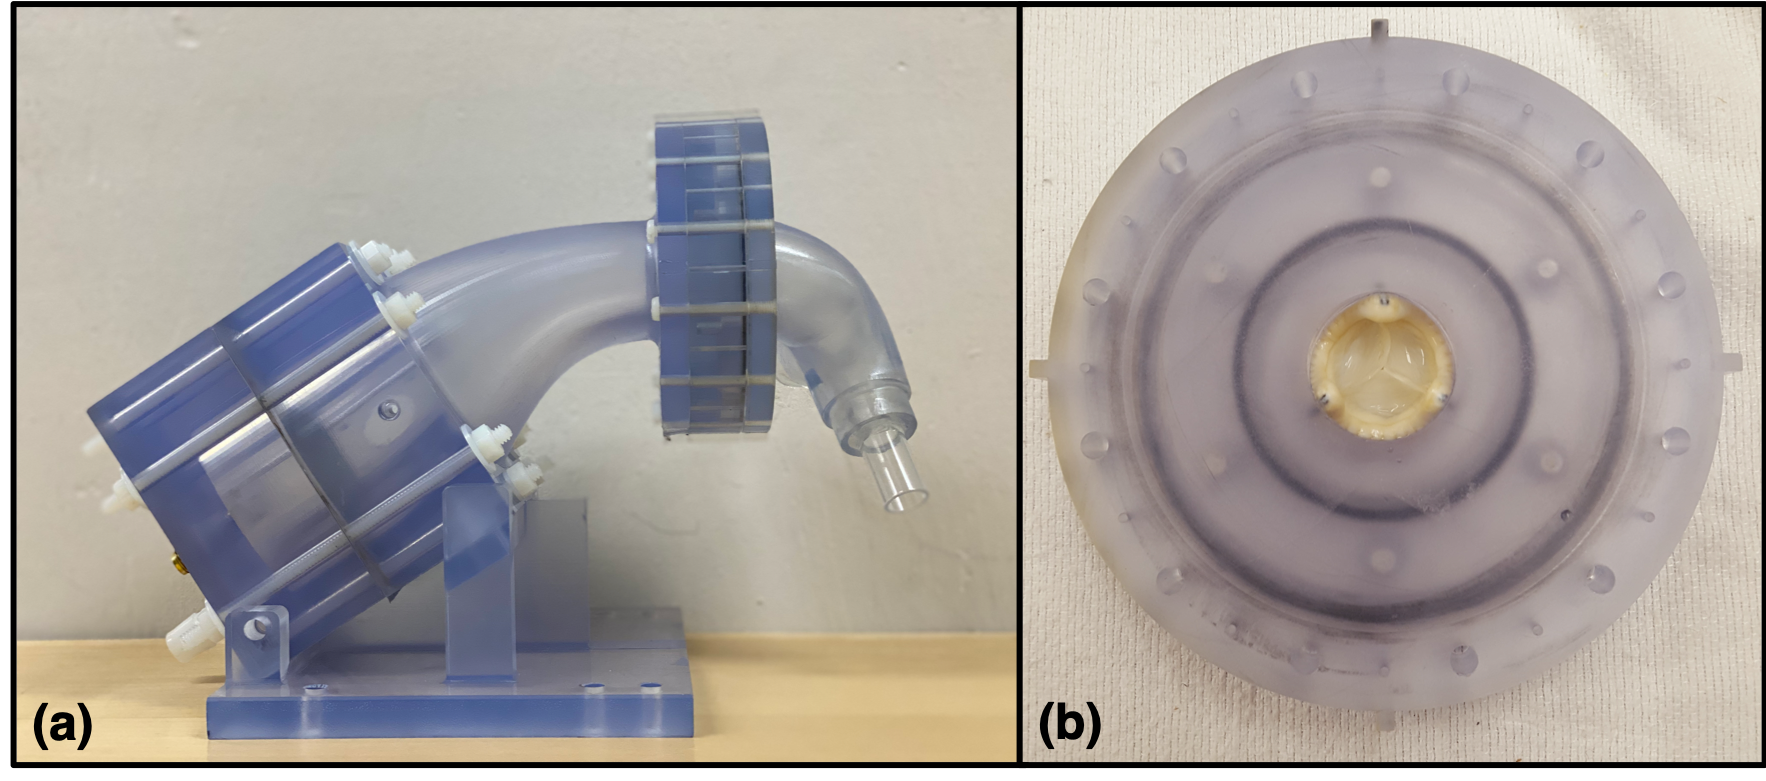

The model was designed in SolidWorks (Waltham, MA) and was manufactured using stereolithography (SLA) with DSM Somos WaterShed XC 11122 resin at the W.M. Keck Center at the University of Texas, El Paso. All components of the model and the valve itself are fully MR compatible. The 3D printed healthy RVOT model is shown in Figure 2a, with all components fully assembled.

The valve used in this experiment was a 25mm Epic valve (Abbott Cardiovascular, Plymouth, MN), which is a porcine bioprosthetic trileaflet aortic surgical valve, which we placed in the pulmonary position. The valve includes support scaffolding at the commissures and a sewing ring that is used to suture the valve to the RVOT vessel in the patient. The valve was implanted into the model using a two-piece component valve-holder piece with a groove that matched the dimensions of the sewing ring on the 25mm Epic valve, which has an estimated internal diameter of 20 mm, as measured via a caliper. This groove was clamped around the sewing ring with the two pieces screwed together to secure the valve (Figure 2b).